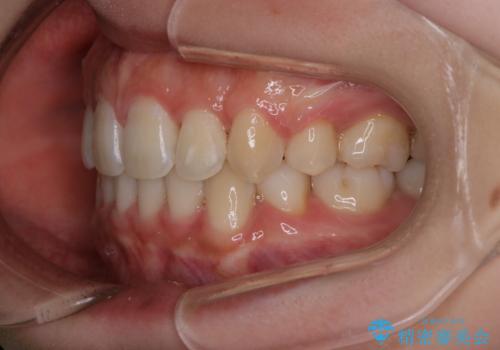

- 口元をさげたいという主訴で来院されました。4番の歯を4本抜歯し、審美装置にて治療をしました。

抜歯をしたことで口元の突出感が改善しました。約2年を予定していた矯正ですが、約1年という短い期間で終了できました。